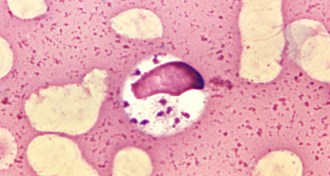

Life’s early traces

Tiny tufts, rolls and crinkles in 3.5-billion-year-old rocks add to a growing body of evidence suggesting that cellular life got a relatively quick start on Earth.